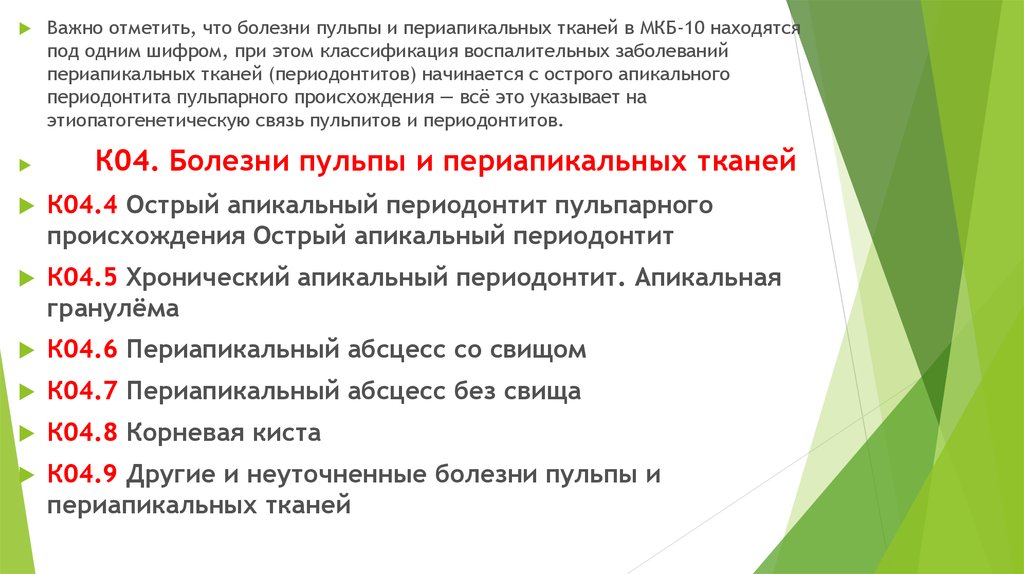

Код мкб 10 атерома головы

Код мкб 10 атерома головы 109 фото